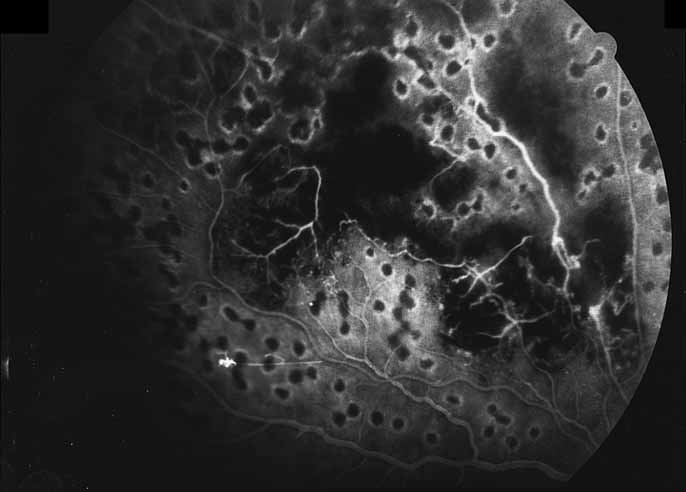

Fig. 12 Acute multifocal hemorrhagic retinal vasculitis. The patient later developed disk neovascularization with vitreous hemorrhage. Note the areas of neovascular leakage from the optic nerve.

Fig. 13 Acute multifocal hemorrhagic retinal vasculitis. The patient underwent scatter laser photocoagulation to the zones of retinal capillary nonperfusion, which resulted in regression of the neovascularization.